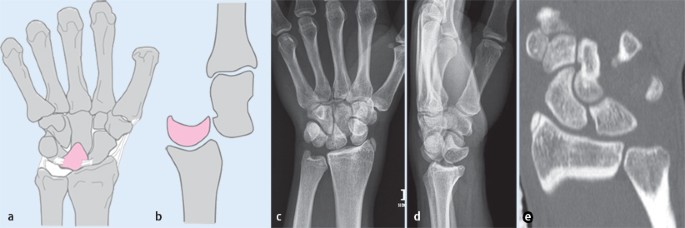

- Röntgenaufnahmen: Röntgenaufnahmen können helfen, den Zustand des Zahns und der umgebenden Knochenstrukturen zu beurteilen. Sie können auch mögliche Frakturen oder Schäden am Zahn aufdecken.

- CT-Scan: Ein CT-Scan kann detaillierte Bilder des Zahns und des umliegenden Gewebes liefern. Dies kann dem Zahnarzt helfen, den genauen Schaden und die Ausdehnung der Luxation zu bestimmen.